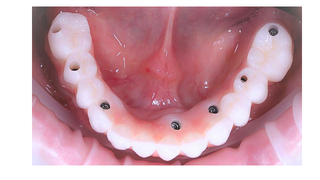

ВСТАНОВЛЕННЯ ТИМЧАСОВОЇ КОРОНКИ.

Встановлення коронки для створення правильного контуру м'яких тканин (ясна).

ПРОТЕЗУВАННЯ – ВСТАНОВЛЕННЯ КОРОНКИ.

Підбирається оптимальний матеріал, форма та розмір коронки, після чого вона встановлюється на абатмент та процес завершений.